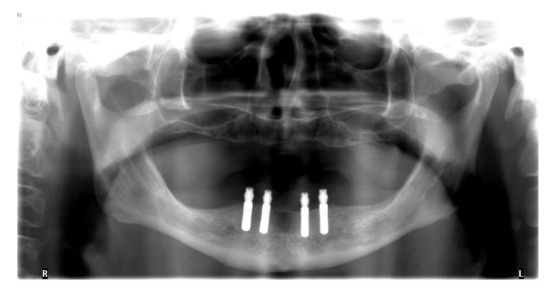

Figure 1.

Orthopantomogram after insertion of four implants in the lower jaw.

The insertion of the implants was planned with a wax-up that was finally transferred into an x-ray template. Digital volume tomography was employed by using the template to plan the positions and types of four interforaminal implants (Bone Level, 3.3 mm × 10.0 mm, Straumann, Basel, Switzerland). Subsequent to the approval of the implant positions, a surgical drilling guide was fabricated from the data. Correct planning of implants is highly important because malpositioned implants can cause esthetical, biological, as well as technical failures [19].